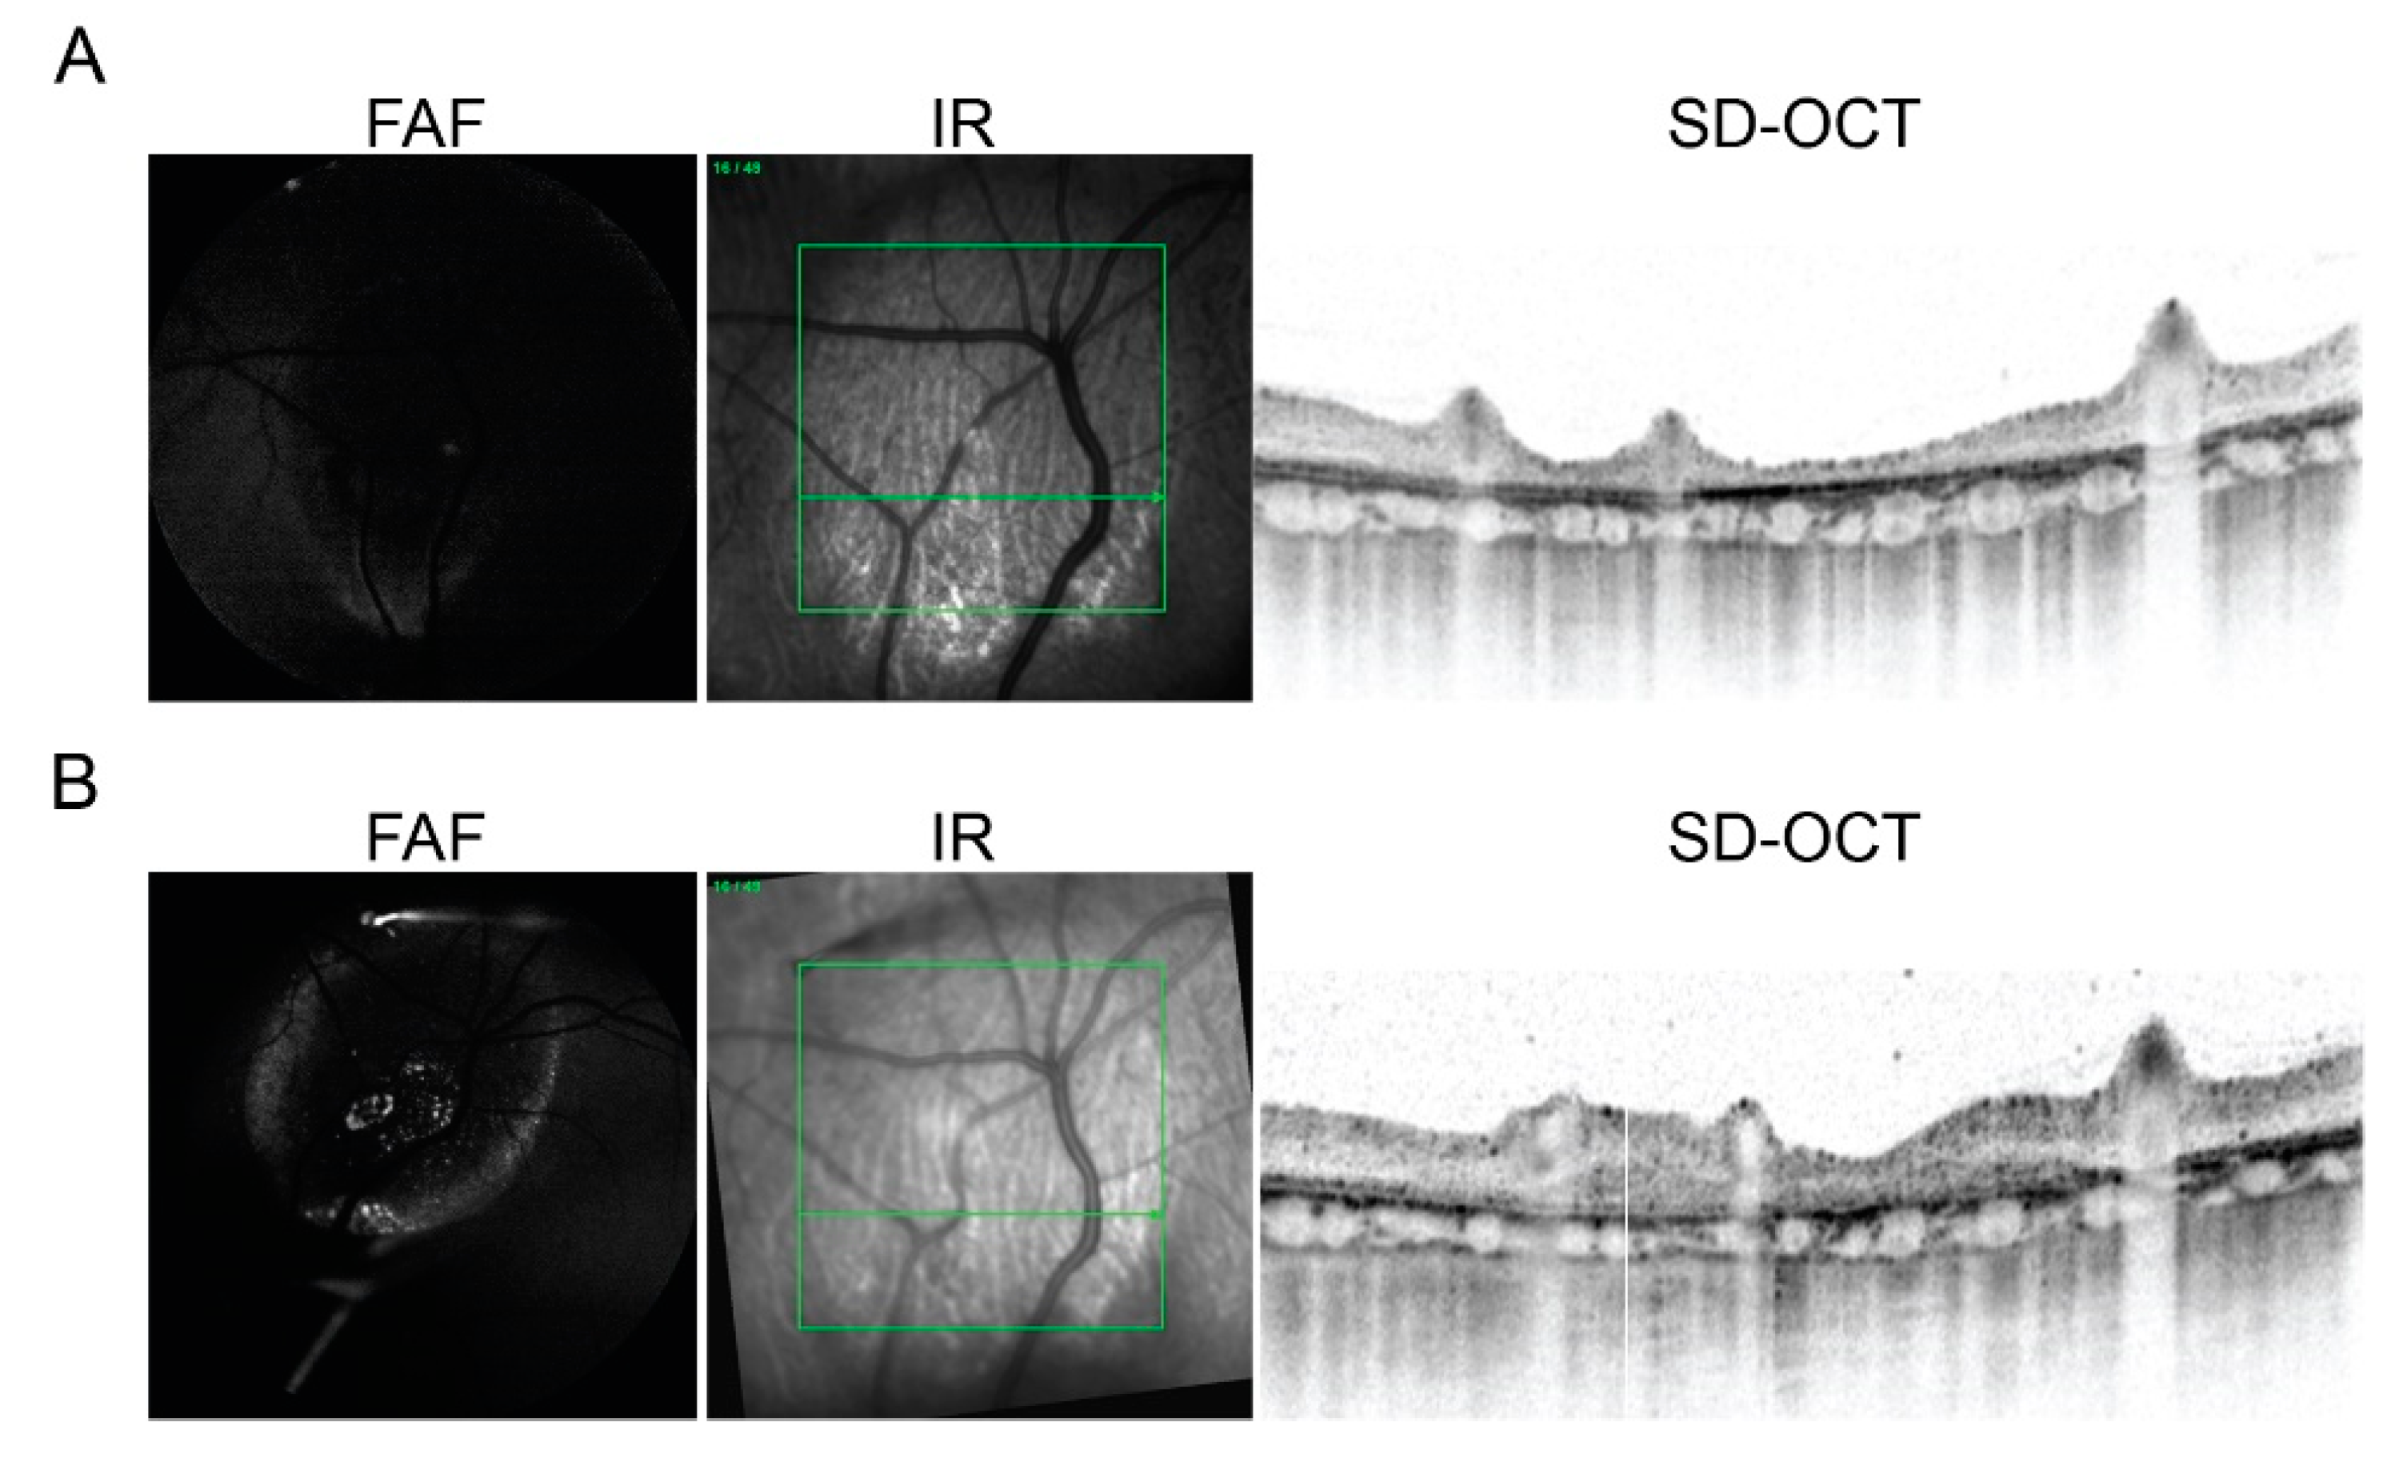

2.3. In Vivo Imaging of Transplanted hiPSC-RPE Cells in the Porcine Eyes